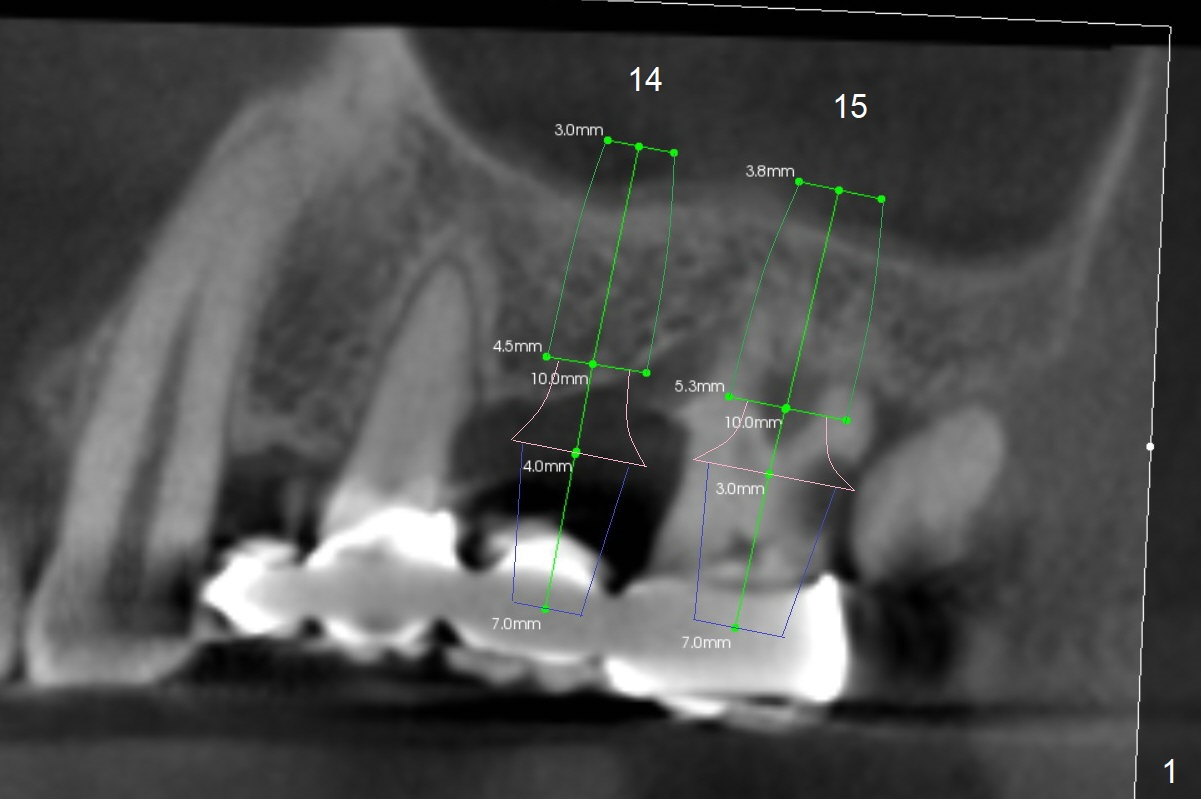

A 57-year-old man has food impaction in the upper left posterior sextant due to caries at #15 and 16 (Fig1). The bridge will be sectioned between 13 and 14. If the cantilever FPD of #12/13 is stable, place #14,15 implants in the normal mesiodistal position using surgical stent. Otherwise the implants should be distal so that there is space to distalize the tooth #13 orthodontically prior to #12 implant placement. Initial depths at #14 and 15 are 7 and 4 mm using IS and SCA kits. Find surgical stent.